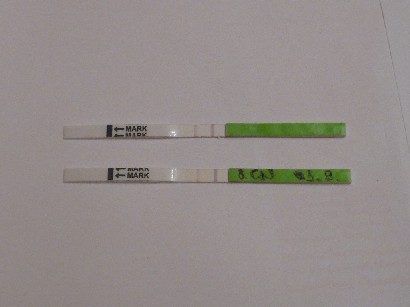

betty: mai tesztre nagyon kiváncsi vagyok, szerintem sem a szurit láthattad a tegnapi csíkon